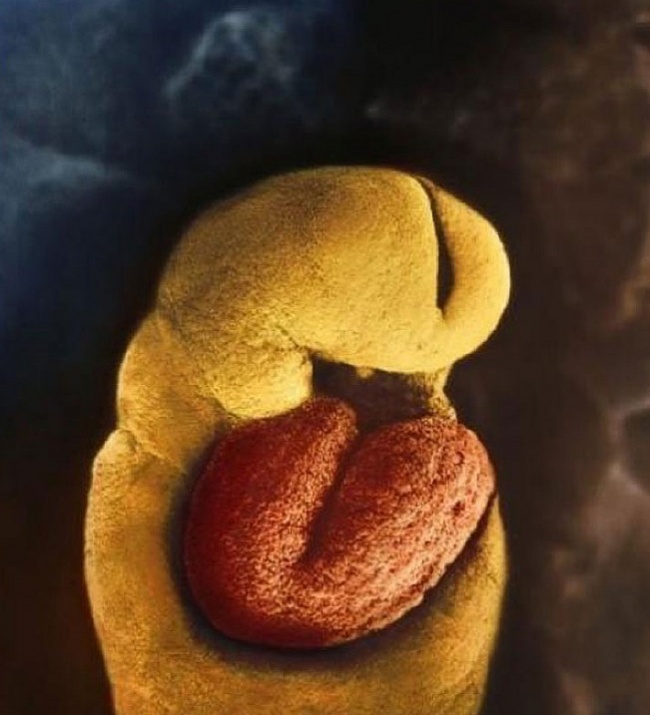

A 18. napon a magzat szíve elkezd dobogni.

Az embrió a 22. napot követően elkezd fejlődni. A képen látható szürke terület lesz később a gyermek agya.

28 nappal a megtermékenyítés után.